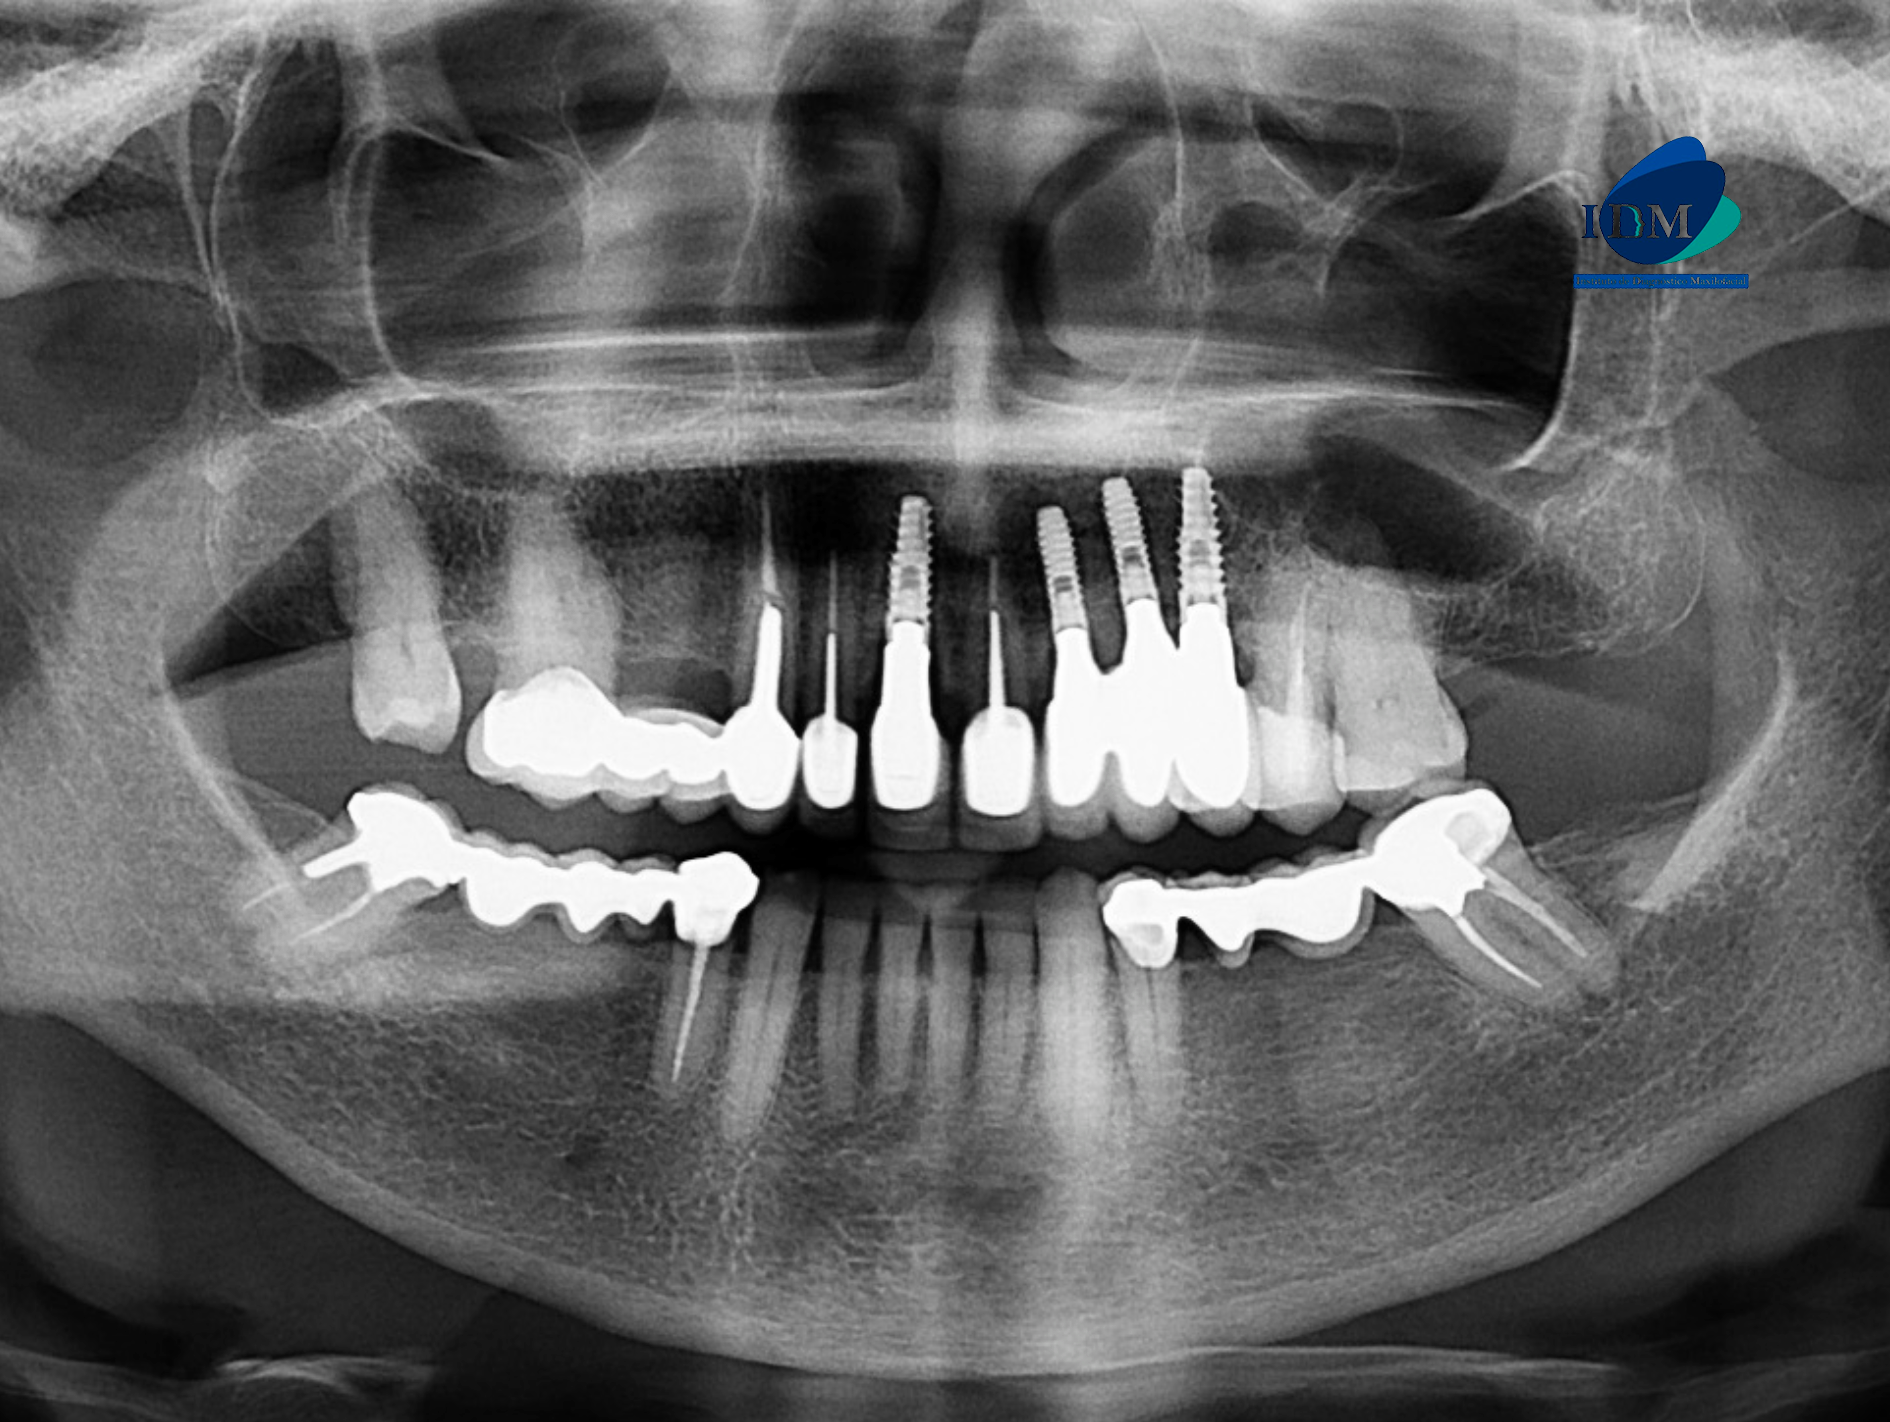

En la radiografía panorámica (Figura 1), se observa edentulismo parcial, múltiples restauraciones protésicas e implantes dentales. Además de un aumento de la densidad ósea en zona de paladar.

Radiografia Panorámica